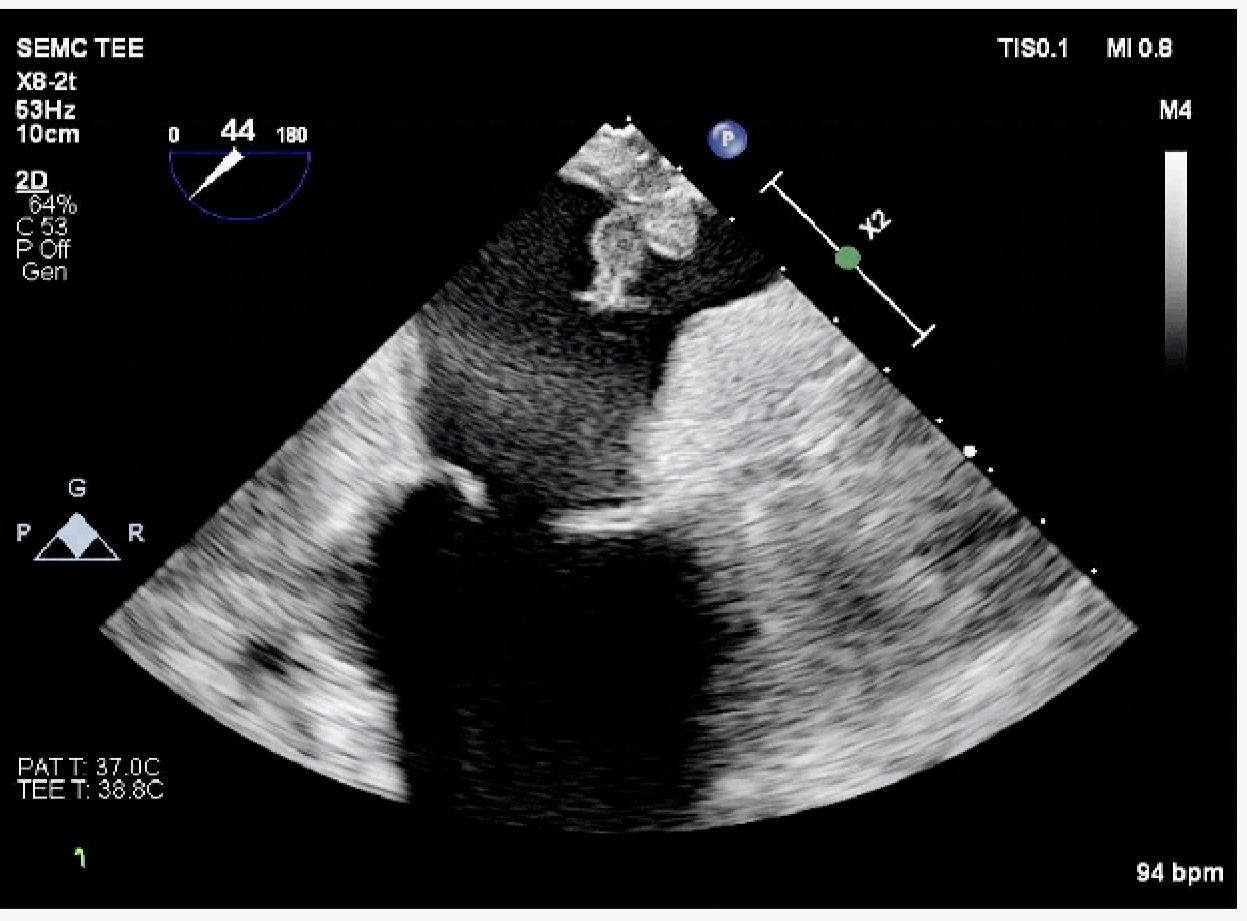

Abstract Body (Do not enter title and authors here): A 67-year-old male with prior CABG (2022), atrial fibrillation, and dual-chamber pacemaker (implanted November 2024) underwent radiofrequency ablation for atrial fibrillation with additional cavotricuspid isthmus ablation for typical flutter in April 2025, continuing Apixaban post-ablation. Thirty-five days later, he presented with sudden-onset slurred speech and left-sided weakness that resolved within 10 minutes. Two hours later, he developed facial droop, aphasia, and left hemiparesis. CT head negative;CTA head/neck showed moderate bilateral carotid stenosis and distal right vertebral artery narrowing. On hospital day two, he developed fever and worsening shortness of breath, requiring ICU transfer for NIV support. CT chest ruled out pulmonary embolism. Blood cultures grew Streptococcus mitis, and broad-spectrum antibiotics were started. He was intubated to facilitate MRI brain, which revealed extensive bilateral supratentorial embolic infarcts with vasogenic edema and microhemorrhages. Transthoracic echocardiogram was inconclusive; transesophageal echocardiography revealed a 1.7 × 1.0 cm mobile echodensity on the roof of the left atrium (Image 1). The left atrial appendage was thrombus-free, and no vegetations were seen on the visible pacemaker lead. Apixaban was discontinued due to cerebral hemorrhage. Despite ICU-level care, the patient developed septic shock, acute kidney injury, and multiorgan failure. After discussion with family, he was transitioned to comfort care and died on hospital day six.

This case illustrates a rare but fatal complication of post-ablation infective endocarditis. While vegetations typically involve valvular surfaces, ablation-induced transmural injury may expose thrombogenic and infectable endocardium. The left atrial roof is an unusual site for vegetation but anatomically plausible following ablation. Streptococcus mitis, a viridans group streptococcus, may preferentially seed areas of prior endothelial injury. Early transesophageal echocardiography plays a critical role in identifying non-valvular vegetations, guiding antimicrobial therapy, and informing anticoagulation decisions. To our knowledge, this is the first reported case of left atrial roof endocarditis following atrial flutter and fibrillation ablation presenting with extensive bilateral septic embolic stroke. Clinicians should maintain a high index of suspicion for atypical IE in the post-ablation period, particularly in patients with cardiac devices.